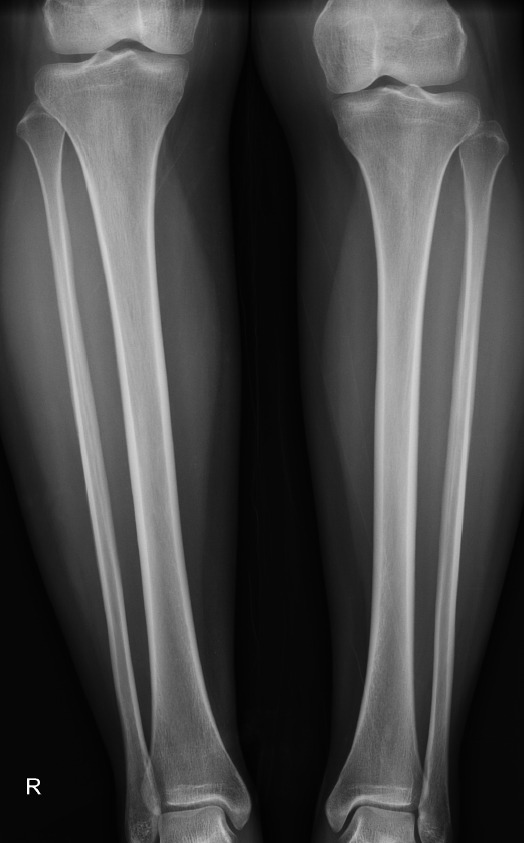

23살 여성

우측 경골이 2.5cm 더  길다. 그 결과로 골반, 척추의 측만증이 발생함.

추정컨대, 우측다리에 피부이상으로 경골이 더 자란듯 함.

1. 우측경골이 2.5cm더 긴상태로 자람.